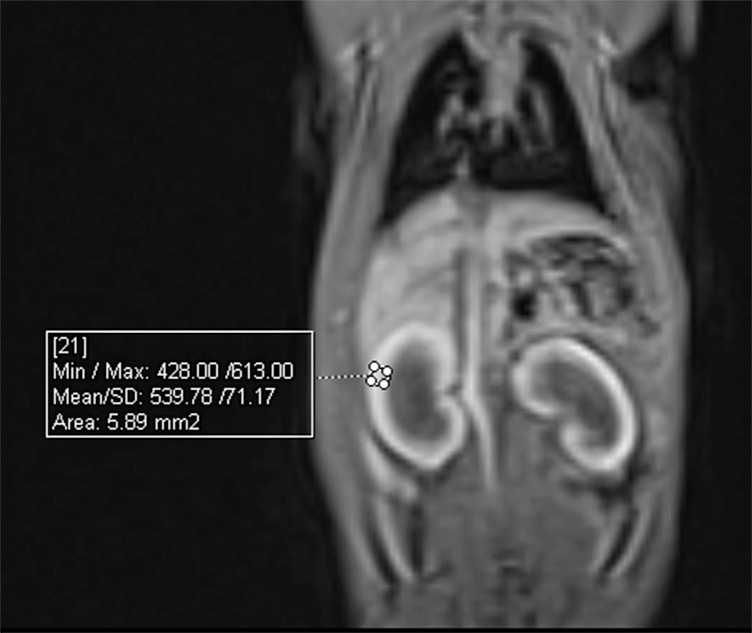

Methods:  Seventy rats (5 animals per group) were included in the sample, and 9 groups received a single dose (0.3, 0.6, and 1.2 mmol/kg) of gadolinium, and 1 group for each dose was sacrificed at the end of the first day, week, and month. Four groups received weekly doses (0.3 and 0.6 mmol/kg) and were sacrificed at the end of 6 and 12 weeks. Measurement of T1 intensities was carried out with postinjection images before sacrifice, and deposition was determined using inductively coupled plasma mass spectrometry.

Results:  The number of injections was associated with increased gadolinium deposition (P <.001) in the kidney. After the weekly injections, the deposited gadolinium levels did not significantly difer between the low and medium doses at the end of the sixth week (P=.067). There was no agreement between the observers regarding the measurement of T1 signal intensity in both single-dose and multidose experiments (P=.263 and P=.307, respectively).

Conclusion:  Deposition was dose dependent in the postinjection stage in contrast to the late stage in which deposition was not associated with dose or number of injections until the 12th week. T1 signal intensity measurement is unreliable for assessing deposition in the rat kidney.